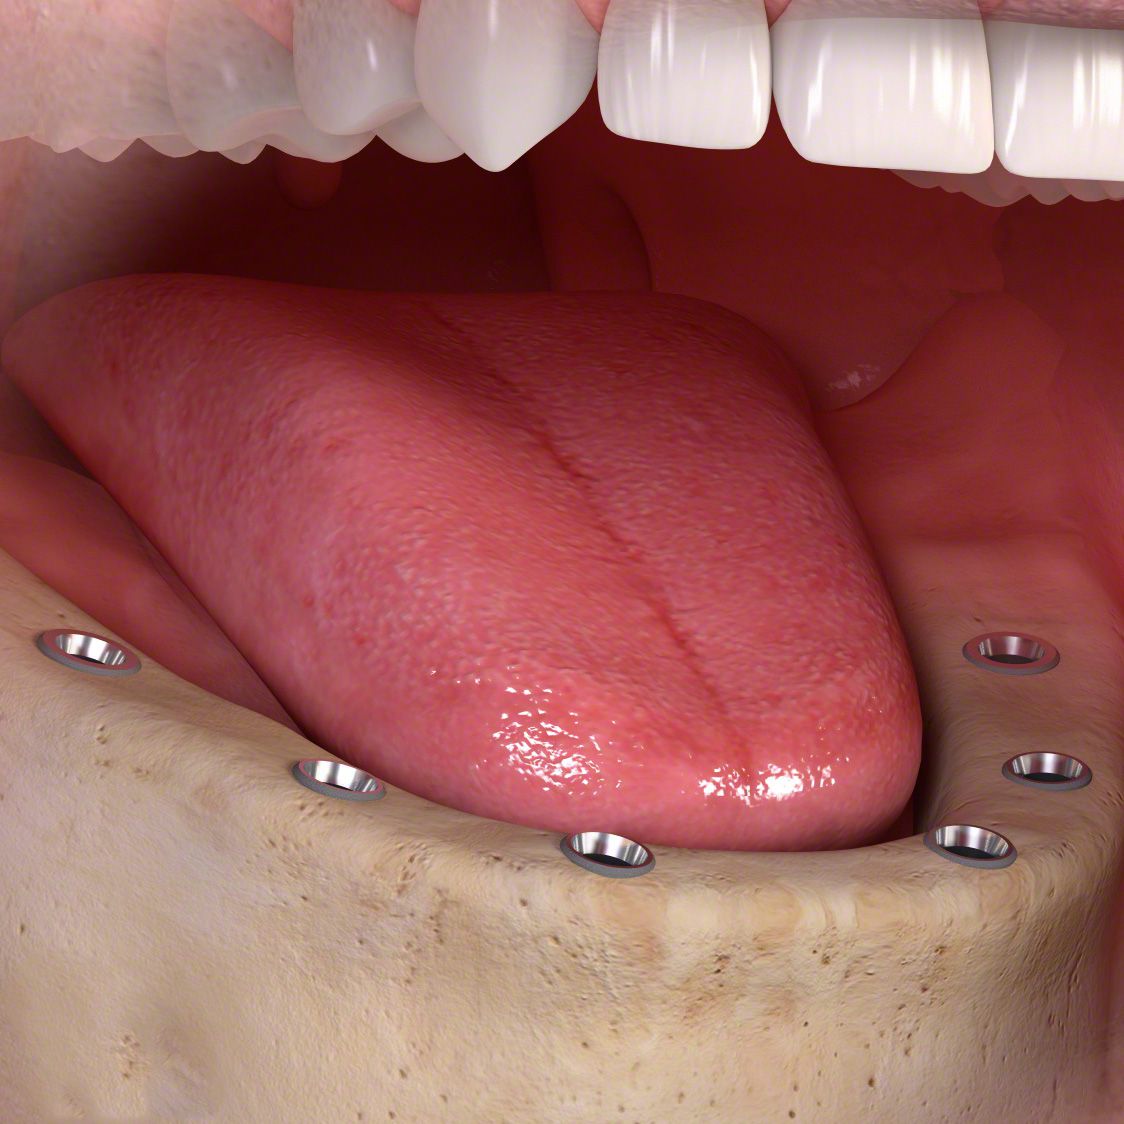

Die entstandene Lücke kann mit einer künstlichen Zahnwurzel, d.h. mit einem Implantat geschlossen werden. Implantate, meist aus Titan oder Keramik, werden dabei in einem kleinen chirurgischen Eingriff in den Kieferknochen eingesetzt. Nach dem Einheilen tragen sie später den eigentlichen Zahnersatz (Kronen, Brücken, Prothesen).

Implantate sind eine langlebige, festsitzende und komfortable Lösung und tragen damit zu mehr Wohlbefinden und Lebensqualität bei. Allerdings brauchen Sie besondere Aufmerksamkeit und Pflege: mit regelmäßiger Prophylaxe – alle 3 bis 4 Monate – werden Sie über viele Jahre Freude an Ihren neuen, festsitzenden Zähnen haben.